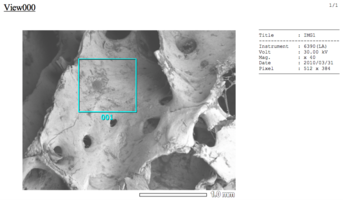

Биоимплантаты аллогенные стерильные губчатые механически и и ультразвуком обработанные.

Фрагмент правильной формы неоднородной поверхности без дополнительных включений и субстанций натурального или синтетического происхождения.

По внешнему виду представляет собой пористый губчатый блок номинального размера.

2. Поверхность и структура материала для изготовления биоимплантатов